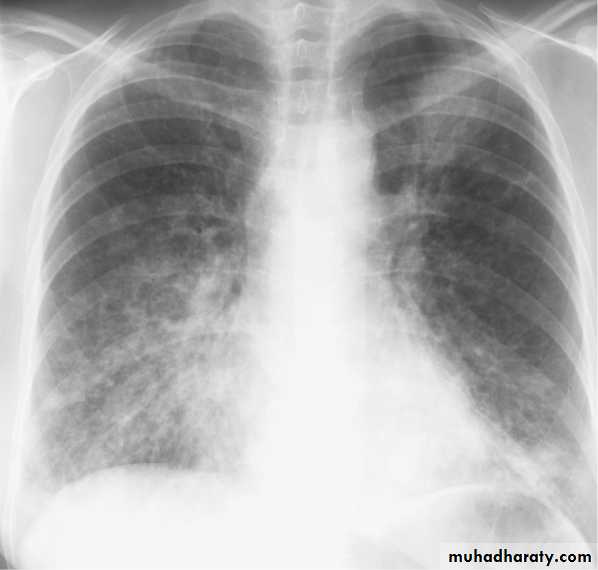

Mycoplasma pneumonia. A 35 year old man presents with nonproductive cough and fever